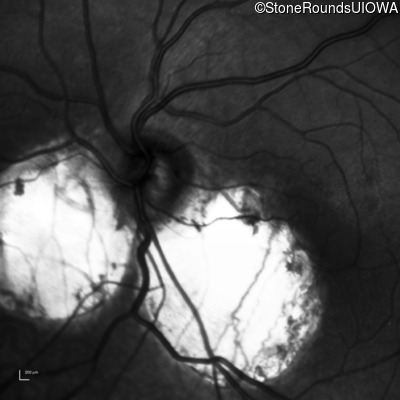

Age at visit: 6 months (Visit 5)